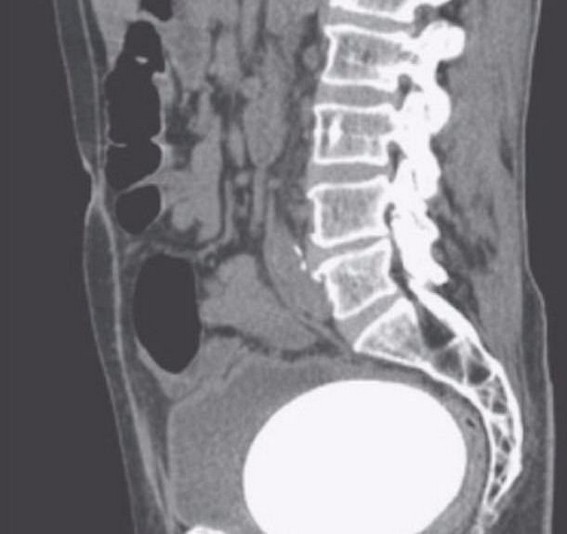

Sau khi làm các xét nghiệm cần thiết, bản quét CT đã cho thấy bệnh nhân có viên sỏi to bất thường trong bàng quang. Sau khi phẫu thuật lấy viên sỏi ra, các bác sĩ xác đinh nó nặng khoảng 770g.

Không chỉ có thế, các bác sĩ còn phát hiện viên sỏi khác nhỏ hơn trong niệu quản trái, ống dẫn nước tiểu từ thận đến bàng quang của bệnh nhân. Viên sỏi này sẽ được phá vỡ bằng phương pháp trị liệu laser.